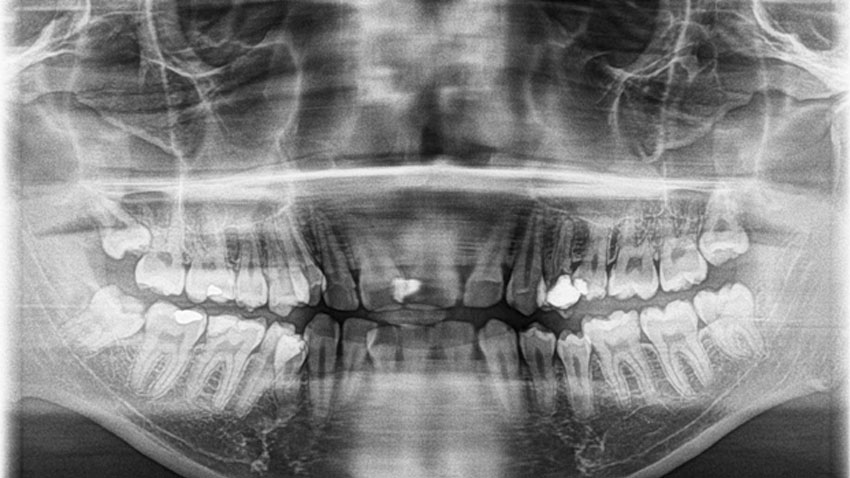

An OPG (Orthopantomagram) is a panoramic scanning dental X-ray of the upper and lower jaw. It shows a flattened two-dimensional view of a half-circle from ear to ear. Panoramic x-rays allow images of multiple angles to be taken to make up the composite panoramic image, where the maxilla (upper jaw) and mandible (lower jaw) are in the viewed area. The structures that are outside the viewed area are blurred. At some stage in your dental treatment, your dentist will likely take an OPG.

An OPG can be used to look for Fractures, Dislocated jaw, Infection, Dentition (teeth). It can also be used for surgical planning.